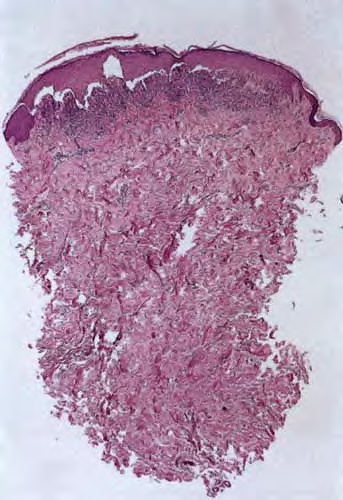

Bullous lichen planus = الحزاز المسطح الفقاعي